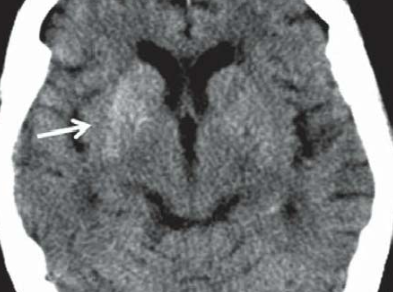

- Hyperdensités du striatum (noyau caudé putamen)